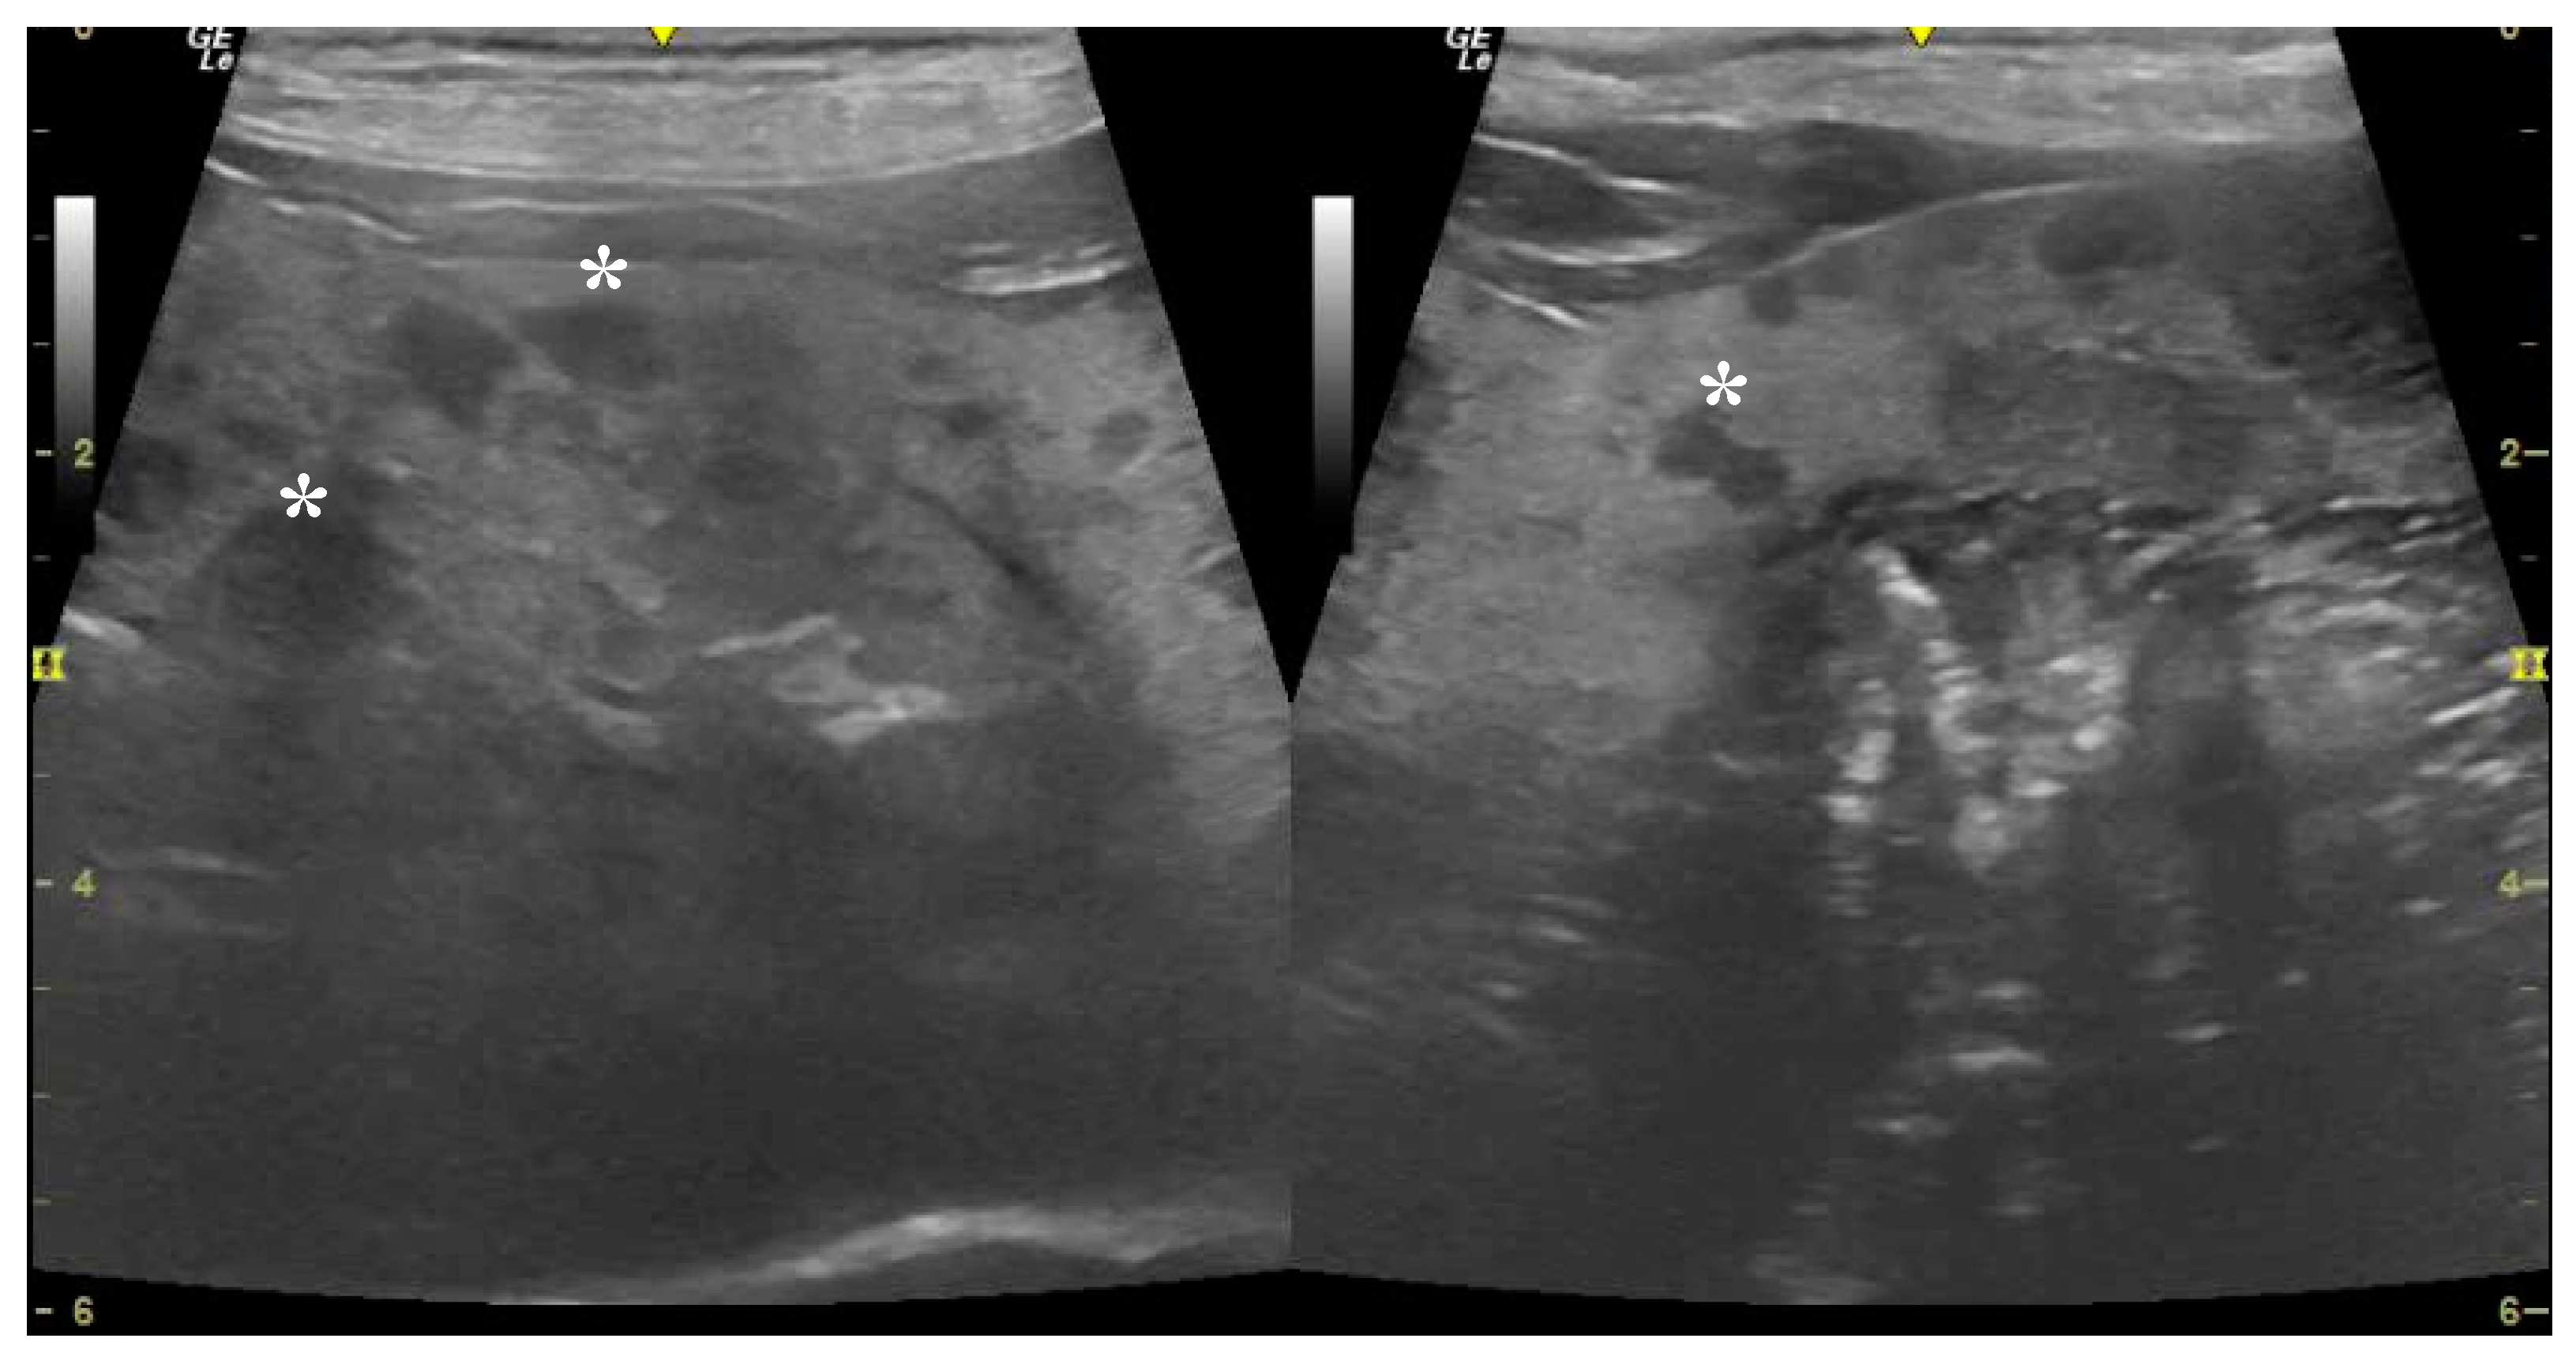

3.2. Ultrasound Examination

| Lesion homogeneity | <0.001 | ||

| Homogeneous (n (%)) | 30 (93.75) | 1 (9.09) | |

| Heterogeneous (n (%)) | 2 (6.25) | 10 (90.90) | |

| Lesion echogenicity | <0.001 | ||

| Hyperechoic (n (%)) | 2 (6.25) | 0 (0) | |

| Hypoechoic (n (%)) | 29 (90.62) | 3 (27.27) | |

| Heteroechoic (n (%)) | 1 (3.12) | 8 (72.72) | |

| Maximum lesion diameter (cm) (mean SD) | 1.23 (0.68) | 4.33 (1.52) | <0.001 |

| Average lesion diameter (cm) (mean SD) | 0.64 (0.42) | 2.6 (1.03) | <0.001 |